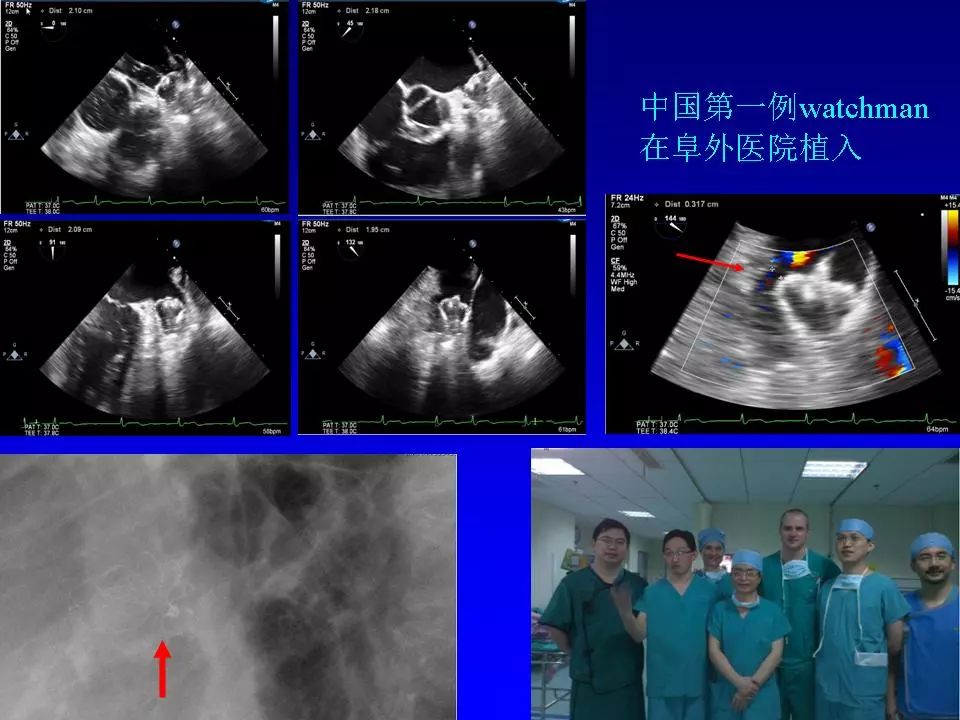

在2018老年冠心病学习班上,阜外医院心律失常中心的方丕华教授从房颤的分类、治疗策略和介入治疗方法入手,与大家分享了房颤介入治疗技术的个体化应用策略